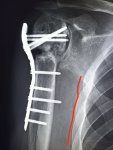

И снова здравствуйте! Сегодня! В этом тредике! Мы будем с вами общатся и играть в доктора! Я буду вам постировать фоточки, а вы угадывать пиздецомы! Я все еще нихуя не успеваю, пытаюсь описать за 25 число, сегодня задержусь наверное после работы опять пытаясь нагнать нагрузку :-(